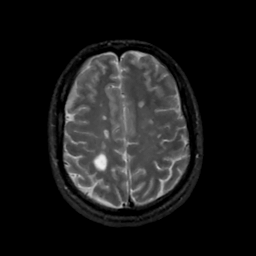

MR Study #12, May 12, 1991 -- Slice #37